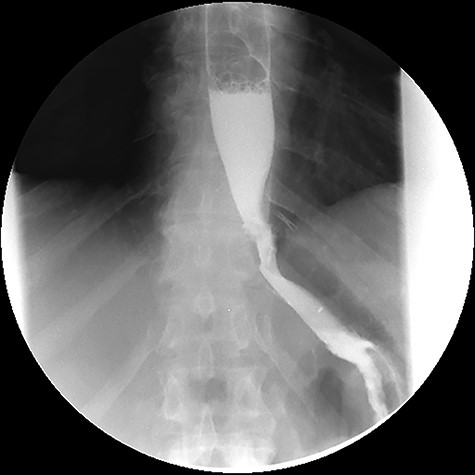

The computed tomography (CT) scan with oral contrast revealed a GGF (see Fig. 1). The upper gastrointestinal endoscopy confirmed a GGF and also demonstrated a stenosis of the gastro-jejunal anastomosis (GJA) (see Fig. 2).

Computed tomography with intravenous contrast images demonstrating a gastro-gastric fistula (arrows). A: axial reconstruction; B: sagittal reconstruction.